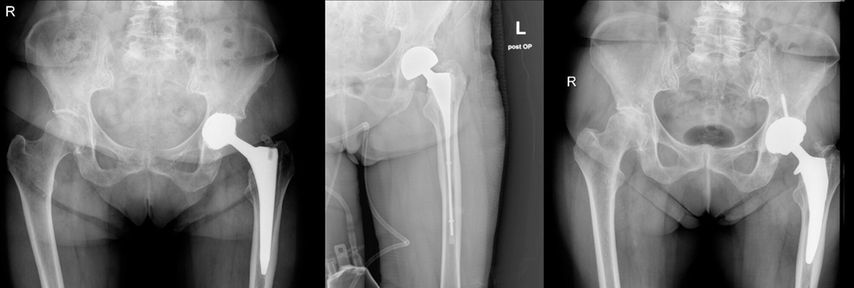

An unserer Abteilung wurde in den letzten 4 Jahren in 13 Fällen ein Downsizing durchgeführt. Gründe für die Revision waren 6 aseptische Lockerungen und 7 periprothetische Infektionen. Es bestanden Typ-II- und Typ-III-Defekte. Abbildung 1 und 2 zeigen zwei Fallbeispiele mit unterschiedlichen Defekttypen. Von den 13 Fällen musste einer aufgrund eines Frühinfektes revidiert werden. Es traten innerhalb von 4 Jahren keine schaftbezogenen Komplikationen auf.

Abb. 1: Downsizing nach 2-zeitigem Wechsel bei periprothetischer Infektion und Typ-II-Defekt nach Paprosky